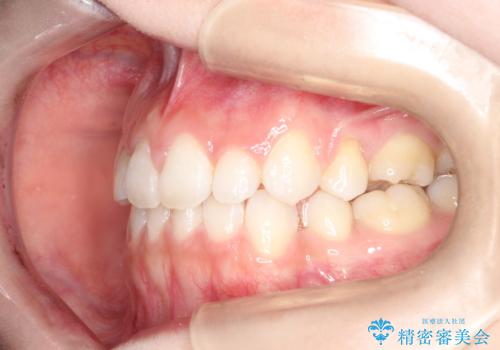

前歯の後戻りを部分矯正で整った歯並びへ

- 矯正治療後の上の前歯の後戻りを気にされて来院されました。

上の前歯のみにブラケットをつけて矯正治療を行いました。